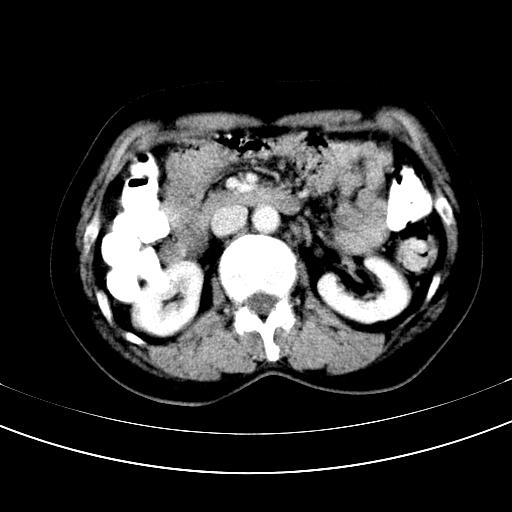

标题: CT12767:肝脏病变请会诊

补充强化片

胃内见充盈缺损,建议行胃镜病理检查,如果胃内无占位,则肝内考虑左叶、尾叶为包膜型肝癌,如有则考虑为转移瘤,左侧肾上腺 明显增大,成结节改变,本人考虑转移瘤可能性大。

肾脏前方的是什么,肾上腺吗,

考虑:胃体小弯侧胃癌(或平滑肌瘤恶化或平滑肌肉瘤)伴肝转移,左侧肾上腺转移不除外.

胃癌肝内转移及肾上腺转移。

胃窦部占位伴肝及左肾上腺转移可能大,建议增强扫描。

谢谢楼主的增强片子,平扫没发现左侧肾上腺的问题很不好意思,可惜片子只有门脉期,所以还只有猜,肝脏的病灶在门脉期部分强化,首先考虑为血管瘤(其他的用一种病不好解释)胃要喝水就好了现在不好说是否有问题,左肾上腺的问题考虑是肿瘤。

做了增强后,可以明确胃是没有肿瘤的,肾上腺也没有肿瘤.肝左叶的病灶首先考虑血管瘤,应该再延迟,肝尾状叶的病灶仍不能排除肝癌的可能性.